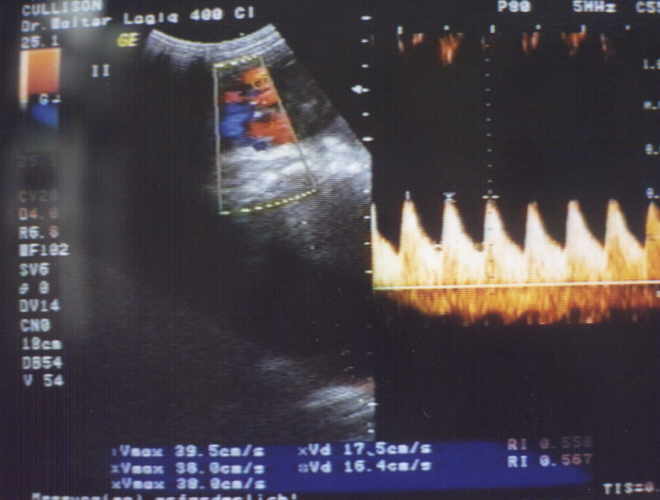

fetale Nabelschnur (normaler Dopplerbefund)

Durch Doppler-Sonographie kann die Durchblutung der Placenta von mütterlicher Seite (Arteria uterina (=Gebärmutterarterie)) und von kindlicher Seite (Arteria umbilicalis = Nabelschnurarterie) dargestellt und gemessen werden. Dabei gibt die Farbe (rot oder blau) die Richtung und die Geschwindigkeit der Durchblutung an. Die aktuellen Blutflussgeschwindigkeiten werden mittels Hüllkurven dargestellt. Die Hüllkurve (Dopplerspektrum) bzw. deren Pulsatilität gibt Aufschluss über die Durchblutung der Placenta und damit über die Versorgung des Kindes.